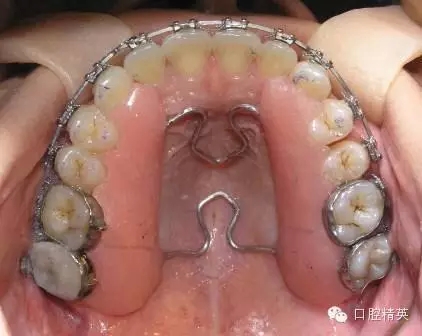

圖5

前面的4張照片是正畸技工制作可摘式擴弓保持器操作步驟,圖5是臨床應用實例。請你注意觀察,說說這種可摘式擴弓保持器有什么作用特點呢?